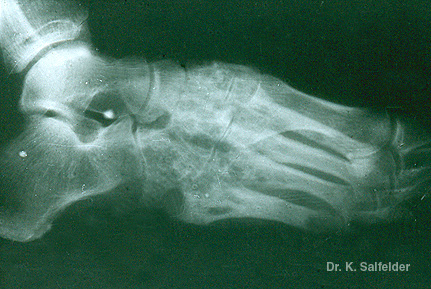

Abb. 16,13: Myzetome

Aktinomyzetom aus Russland. Roentgenologisch eine ausgedehnte Osteomyelitis